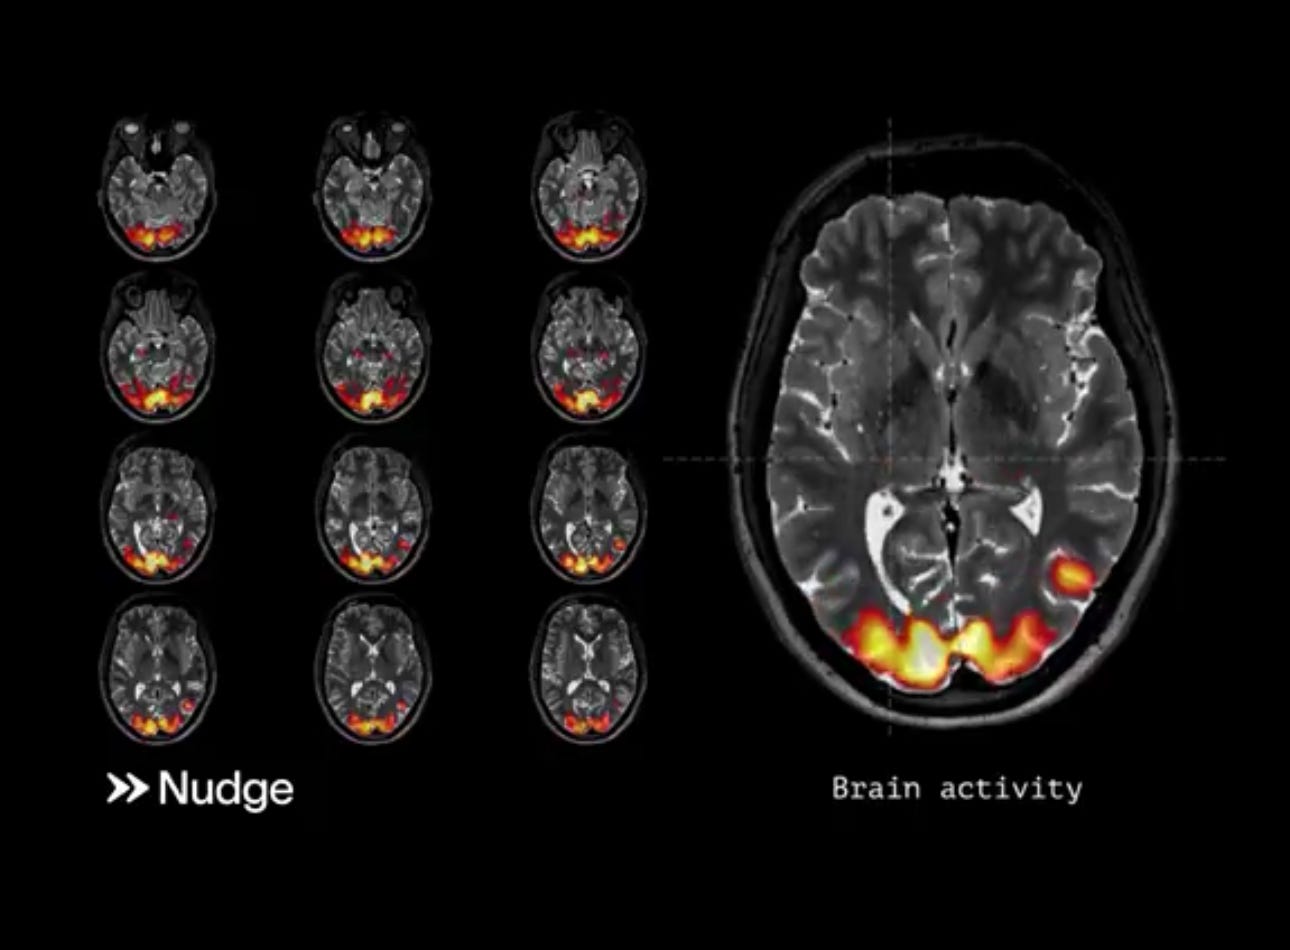

nudging ๐ง

@nudge released a hype video for their focused ultrasound product w some fancy graphics ๐ big fans of ultrasound as a future modality for neurotech